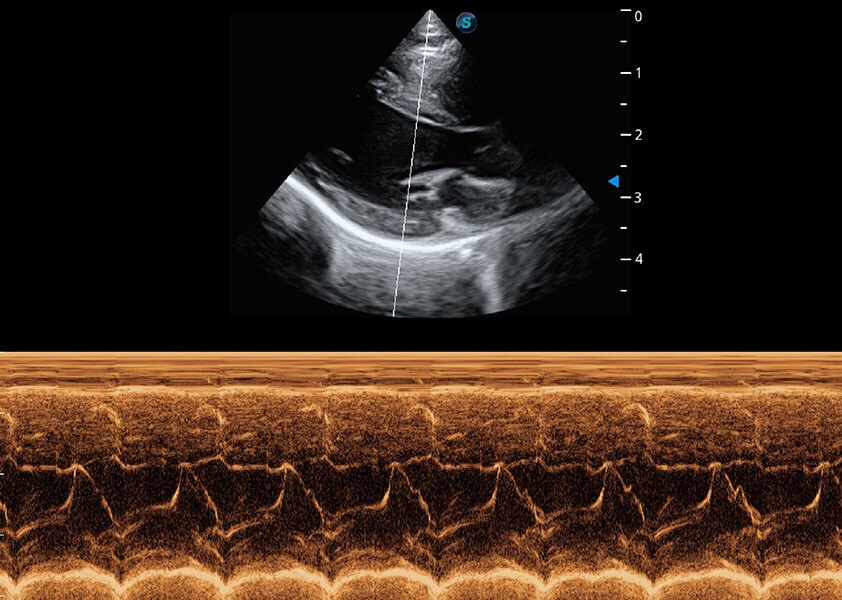

ProPet 60 作為一款高端臺(tái)式動(dòng)物超聲設(shè)備,為動(dòng)物醫(yī)生的日常診斷提供了一系列貼合動(dòng)物臨床需求、解決臨床實(shí)際問(wèn)題的高級(jí)成像功能。憑借全系列高清探頭,滿足醫(yī)生對(duì)腹部、心臟、生殖、淺表、肌骨等成像的所有需求,切實(shí)幫助您提升檢查效率,提高診斷信心。